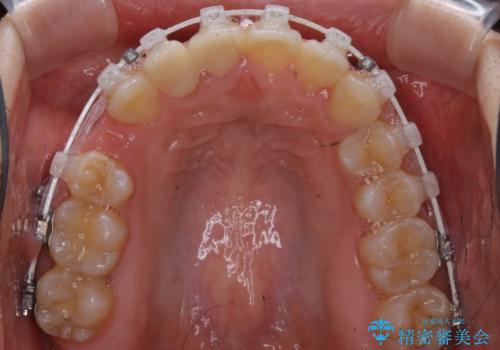

- ワイヤー矯正 審美装置

右上の2番目の前歯が奥に入っている状態で、かぶせてあったため左に比べて短いセラミックになってしまっていました。

矯正治療で根の向きも修正したため、左右対称に審美的なセラミックを入れることができました。

右下の隙間を閉じるため、歯の数を合わせるため、右上の小臼歯を一本抜歯しています。